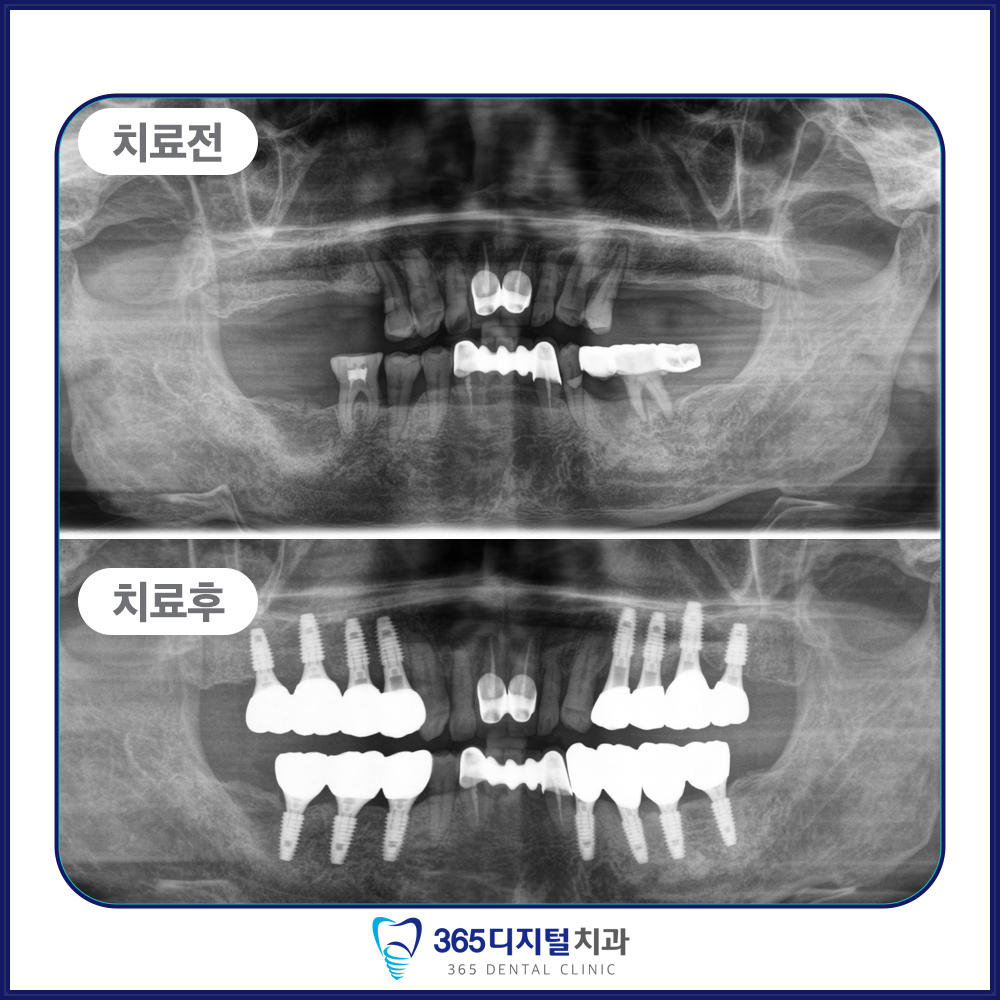

임플란트는 단순히 인공치아를 심는 것이 아닌,

환자의 삶의 질을 회복하는 진료라고 생각합니다.

계획된 진단과 세밀한 설계,

그리고 환자 개인의 구강 구조에

맞춘 접근이 중요합니다.